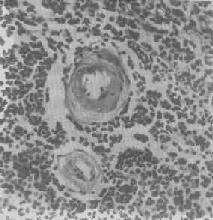

图1-21 肾近曲小管上皮细胞玻璃样小滴变

上皮细胞胞浆内出现大小不等的均质圆形小滴